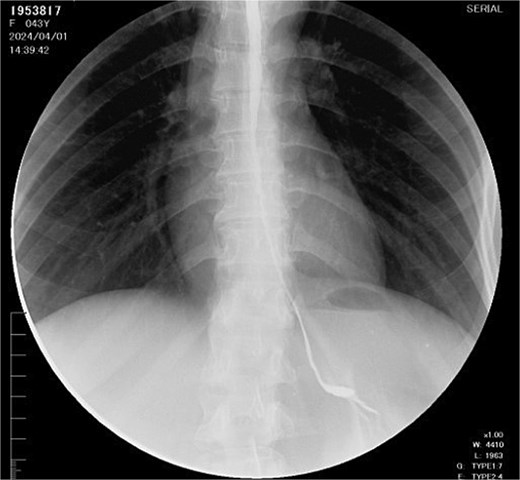

During follow-up, the patient developed complete esophageal stricture (Fig. 1) with absolute oral intolerance, leading to prolonged dependence on jejunal feeding. This resulted in progressive malnutrition, generalized sarcopenia, and a body mass index of 15 kg/m2. Given failure of endoscopic management, definitive esophageal reconstruction was indicated. Preoperative outpatient optimization included high-calorie enteral supplementation and monitoring of albumin, prealbumin, and total protein levels. Psychiatric evaluation confirmed emotional stability and adherence to pharmacologic treatment, clearing her for surgery.